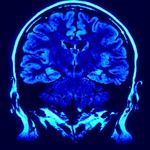

“As we get older, we all lose a little gray-matter volume and white-matter integrity, but in alcoholics, those areas break down more quickly. It looks like accelerated aging,” says Edith Sullivan, a professor of psychiatry and behavioral science at Stanford University.

Modern brain scanning technology shows that excessive alcohol use over long periods of time can actually damage white-matter fibers that connect the various areas of the brain together, according to the article. It can also alter brain structure, negatively affecting gray-matter cells responsible for:

Brain scanning allows doctors to diagnose “alcohol-induced neurocognitive disorder” and “alcohol-related dementia.” Researchers point out there is no way of knowing the threshold that, when crossed, could result in the aforementioned health problems, the article reports. Alcohol affects everyone differently, and there are a number of factors to consider when determining the effects of excessive use, such as: